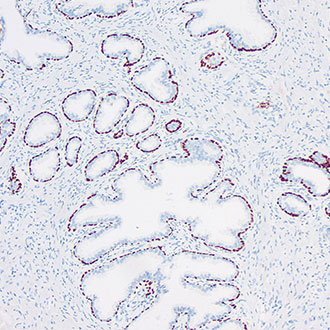

CK19

CK19 -